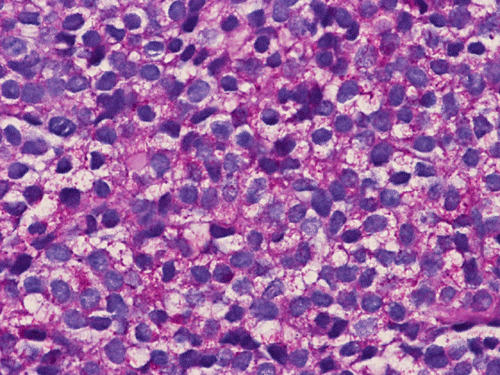

Pathology of the Case: Essentially, this is a small blue cell tumor with focal necrosis (Panel A and B). The nuclei are rather monotonous. Please note that the nuclei are slightly larger than most so-called small blue cell tumor such as small cell carcinoma of the lung. The tumor arrange in solid sheets without any pattern formation. There is a gap in between the cells. This is not uncommon in Ewing sarcoma. However, this pattern can also be seen in hematopoietic tumors such as lymphoma and plasmacytoma. In some areas, some of the tumor cells have a small rim of cytoplasm and some of these rims appear to be formed by fused minute bubbles (Arrow in Panel C). Results of speical stains, immunohistochemistry and molecular studies are as follow:

First, although it is composed of small blue cells, the nuclei are marginally larger than other small blue cell tumors such as small cell carcinoma or medulloblastoma. Their nuclei are also slightly less crumbled after fixation, less hyperchromatic, and have slightly more open chromatin. A small nucleolus can be seen in many nuclei. The nuclei seems to be more monotonous on cytologic (squash or touch preparation) and crush effects on nuclei (smearing of nuclei) is far less common than other small blue cell tumors. Histologically, it is not uncommon for Ewing's sarcoma to have areas of more densely packed areas with hyperchromatic nuclei and these areas are embedded within a slightly less densely packed area with more open nuclei (Image 1 below). On cytologic preparations, small vacuoles may be present in the cytoplasm. These vacuoles are glycogen granues which could be partially washed out during processing as glycogen has a low aqueous solubility and are typically not entirely washed out during processing (arrow in image 2 below).  These vacuoles can be seen in both hematoxylin and eosin stained and Diff-Quick stained cytologic preparations but Diff-Quick works better [Click here to see a case]. Together with the appropriate clinical information, these histologic features are highly suggestive of Ewing's sarcoma.

1. Hematoxylin and eosin stain, permanent section

Note the densely packed areas with hyperchromatic nuclei embedded in a background of nuclei with less hyperchromatic nuclei.

Ewing sarcoma belongs to the family of non-hematologic small round cell tumor characterize by small, undifferentiated, cells with hyperchromatic nuclei. Rosettes similar to Homer Wright rosettes are occasionally present but tumor cells usually arrange in solid sheets. Densely packed solid sheets of small round cells with minimal to no interlacing collagenous collagen or stromal component is the classic appearance. These tumors are richly vascularized by a delicate network but it is not obvious because of compression of vessels by tumor cells. Typically, no inflammatory cells are present. Necrosis is a typically present.

Tumor cells are fairly uniform and have a small amount of cytoplasm typically in the form of a thin rim. Intercellular gaps that are often seen in hematopoietic neoplasms may be present. Cytoplasmic vacuoles corresponding to the glycogen vacuoles can be well appreciated in cytologic preparations. However, it is hard to differentiate them from fixation artifacts in permanent sections. Ewing sarcoma typically contains a good amount of glycogen that are well demonstrated by PAS stain with and without diastase pre-digestion. The nuclear chromatin is finely granular. Although it is a small round cell tumor, its nuclei tend to be marginally larger and less crumbled than many of the other small round cell tumors such as small cell carcinoma. It is common to have geographic patches of cells with open chromatin alternating with areas with closed chromatin leading to a biphasic dark cells and light cells pattern. Small but identifiable small to moderately sized nucleoli. Large and prominent nucleoli can be seen in large cell Ewing sarcoma. Otherwise, large and prominent nucleoli are not typical for Ewing sarcoma.